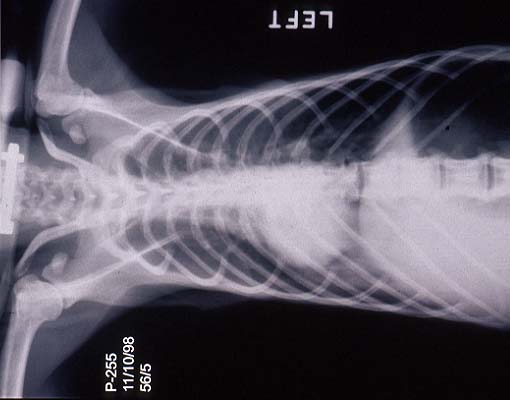

- Case 23-3. The A/P thoracic radiograph shows marked

right sided deviation of the cardiac silouette. The lateral thoracic

radiograph shows diffuse fluid density in dorsal lung fields.

- Thoracic radiographs demonstrated an increased pulmonary

interstitial pattern with air bronchograms bilaterally. The cardiac

silhouette was shifted to the right. Abdominal radiographs demonstrated

hepatomegaly and the presence of excessive gas in the stomach,

small intestine, and colon. Supportive treatment, including oral,

subcutaneous, and intravenous fluids, antibiotics, and vitamins

were administered, but response to treatment was minimal and

the monkey was euthanized in late 1998.